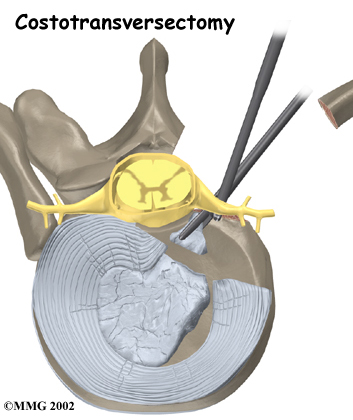

Costotransversectomy

Surgeons use to open a window through the bones that cover the injured disc. Operating from the back of the spine, the surgeon takes out a small section on the end of two or more ribs where they connect to the spine. (Costo means rib.) Then the bony knob on the side of the vertebra (the transverse process) is removed. (Ectomy means to remove.) This opens a space for the surgeon to work. The injured portion of the disc that is pressing against the spinal cord is removed (discectomy) with small instruments. Surgeons take extreme care not to harm the spinal cord.